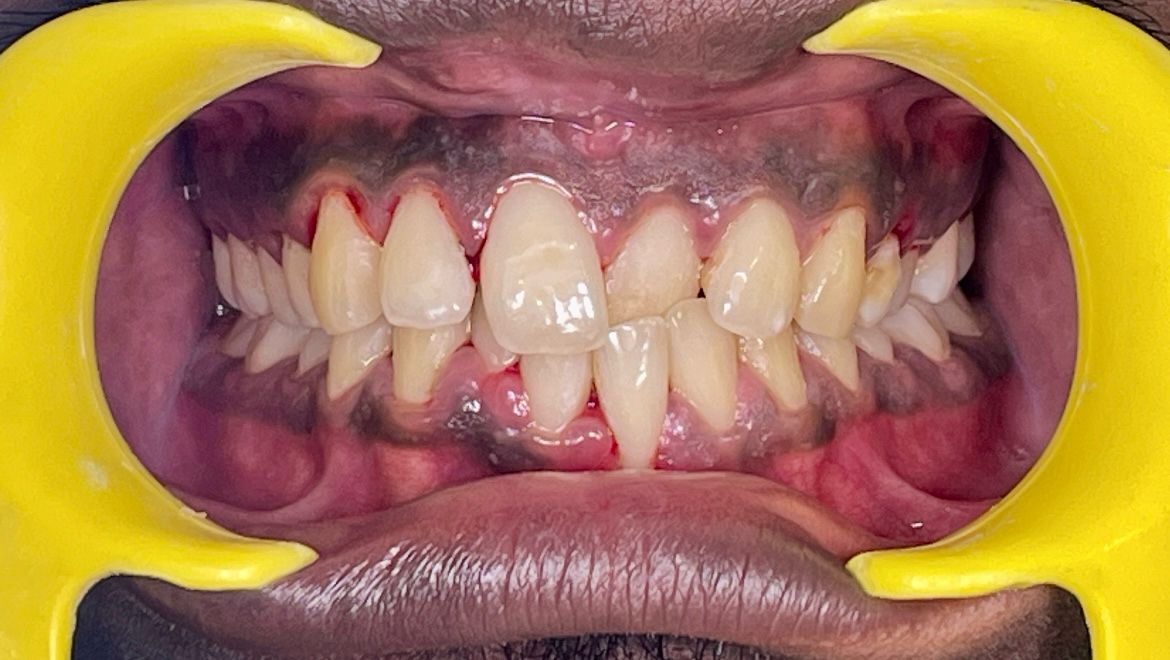

Before Treatment

Before

After Treatment

After

Spacing and Alignment

Duration: 8 months

Aligners: 22 sets

"I honestly didn’t think clear aligners could fix my crowding this fast. I was always self-conscious about my front teeth overlapping, but after just 8 months, the difference is night and day. The best part was that no one even noticed I was wearing them during my meetings. It took about 20 sets in total, and the process was way more comfortable than I expected. If you're on the fence, just do it—my confidence is finally back!" — Rohan S.